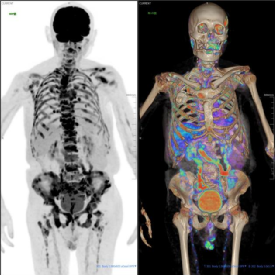

影像学佐证

(附PET/CT图像:前列腺前部正中局灶性高代谢灶SUVmax6.80、全身骨骼多发高代谢灶及纵隔及肺门多发淋巴结异常摄取。)